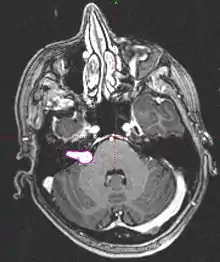

- Imaging: MRI with gadolinium can detect tumors as small as 1-2mm. Seen as an enhancing lesion “ice cream cone” in the region of internal acoustic canal or a “dumbbell” extending into the foramen magnum.